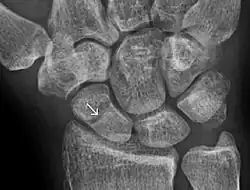

Scaphoid fractures occur in three locations: (A) Distal tubercle, (B) waist, and (C) proximal pole.

Fractures of scaphoid can occur either with direct axial compression or with hyperextension of the wrist, such as a fall on the palm on an outstretched hand. Using the Herbert classification system, there are three main types of scaphoid fractures. 10%-20% of fractures are at the proximal pole, 60%-80% are at the waist (middle), and the remainder occur at the distal pole.[4][7][8]